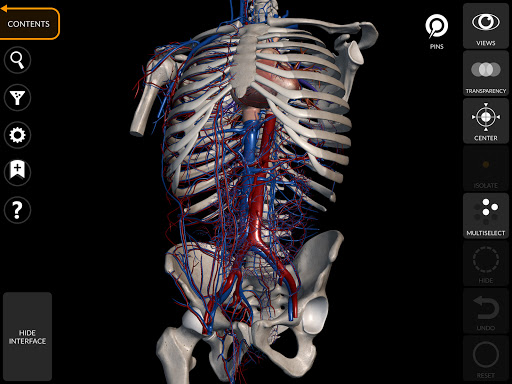

"Anatomía - Atlas 3D" permite estudiar la anatomía humana de forma fácil e interactiva.

A través de una interfaz sencilla e intuitiva es posible observar cada estructura anatómica desde cualquier ángulo.

Los modelos anatómicos 3D son especialmente detallados y con texturas de hasta una resolución de 4k.

La subdivisión por regiones y las vistas predefinidas facilitan la observación y el estudio de partes individuales o grupos de sistemas y las relaciones entre los diferentes órganos.

MODELOS ANATÓMICOS 3D

• Sistema musculoesquelético

• Sistema cardiovascular • Sistema

nervioso • Sistema respiratorio • Sistema digestivo • Sistema urogenital (masculino y femenino) • Sistema endocrino • Sistema linfático • Sistema ocular y auditivo CARACTERÍSTICAS • Interfaz sencilla e intuitiva • Rotar y hacer zoom en cada modelo en el espacio 3D • Opción para ocultar o aislar uno o varios modelos seleccionados • Filtro para ocultar o mostrar cada sistema • Función de búsqueda para encontrar fácilmente cada parte anatómica • Función de marcador para guardar vistas personalizadas • Rotación inteligente que mueve el centro de rotación automáticamente • Función de transparencia • Visualización de músculos a través de niveles de capas desde las superficiales hasta las más profundas • Al seleccionar un modelo o un pin, aparece el término anatómico relacionado • Descripción de los músculos: origen, inserción, inervación y acción • Mostrar/ocultar interfaz de usuario (muy útil con pantallas pequeñas) MULTILINGÜE • Los términos anatómicos y la interfaz de usuario están disponibles en 11 idiomas: latín, inglés, francés, alemán, italiano, portugués, turco, ruso, español, Chino, japonés y coreano • Los términos anatómicos se pueden mostrar en dos idiomas simultáneamente REQUISITOS DEL SISTEMA • Android 8.0 o posterior, dispositivos con al menos 3 GB de RAM Reversi